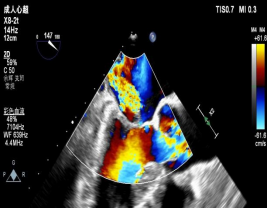

在浙大二院王建安教授、刘先宝教授的指导下,修建成团队携手我院麻醉科、心外科等科室如期开展手术。手术在患者全麻状态下进行,经股静脉入路,穿刺房间隔后在经食道超声和X射线引导下将瓣膜夹器械输送到左心室。与单纯A2区脱垂相比,这两例病人的手术难度明显高出很多。第一例患者由于返流机制复杂,手术团队认为单纯夹合脱垂瓣叶远期效果可能不佳,经反复模拟夹闭,最后选择特殊型号器械捕捉和钳夹二尖瓣前叶和后叶并关闭瓣膜夹。术后二尖瓣瓣口由单孔变成双孔,经食道超声反复确认手术效果后,最终释放二尖瓣瓣膜夹。第二例患者为A1区脱垂,由于A1区存在大量腱索和乳头肌,操作风险和难度明显高于A2区脱垂,需要术者对心脏解剖结构了然于胸,在狭小空间内准确定位瓣膜夹的位置和角度,为了达到最佳的效果,手术团队先后三次模拟操作到位进行夹闭,终于在术者的精细调整下,瓣膜夹到达最佳位置,调整至完美的角度,同时没有累及腱索和瓣叶,准确捕捉瓣叶后成功将A1区脱垂部位夹闭,即刻二尖瓣反流程度显著下降由术前的4+即刻下降到1+,左房内压力显著下降。两例复杂经导管二尖瓣修复手术顺利完成,术后患者即刻清醒,气促明显好转,心脏杂音消失。二位患者精神状态良好,24小时内下地活动,将不日出院。

▲术前与术后彩超结果